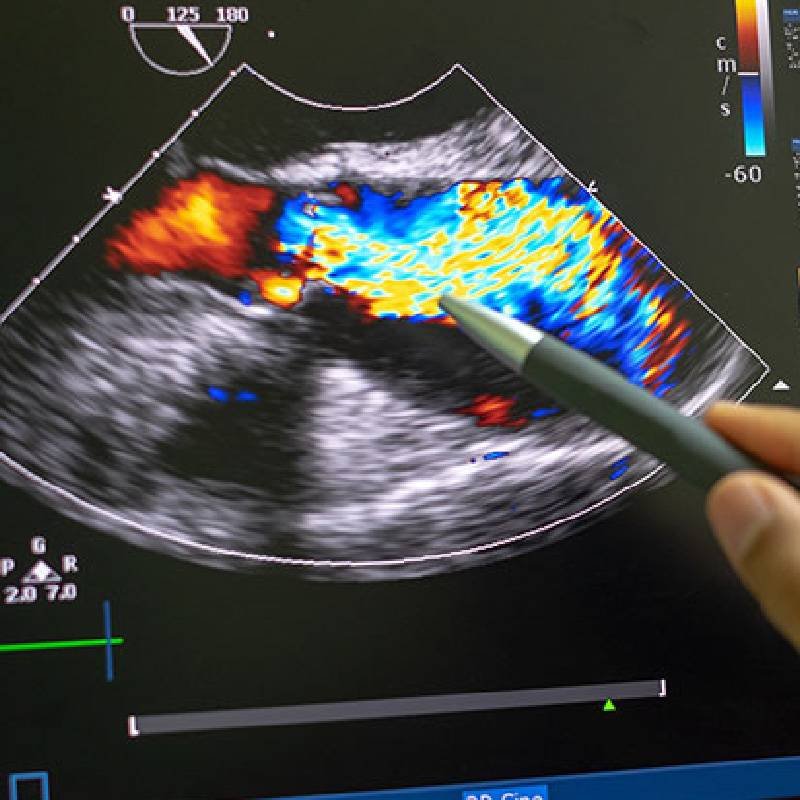

Doppler Carotídeo

Este procedimiento ayuda a diagnosticar:

– Pacientes que han sufrido de un accidente cerebrovascular (derrame cerebral.)

– Oclusión parcial o total de las arterias del cuello.

– Masas en los vasos del cuello (paraganglioma carotídeo).

– Lesiones traumáticas vasculares (pseudoaneurismas).